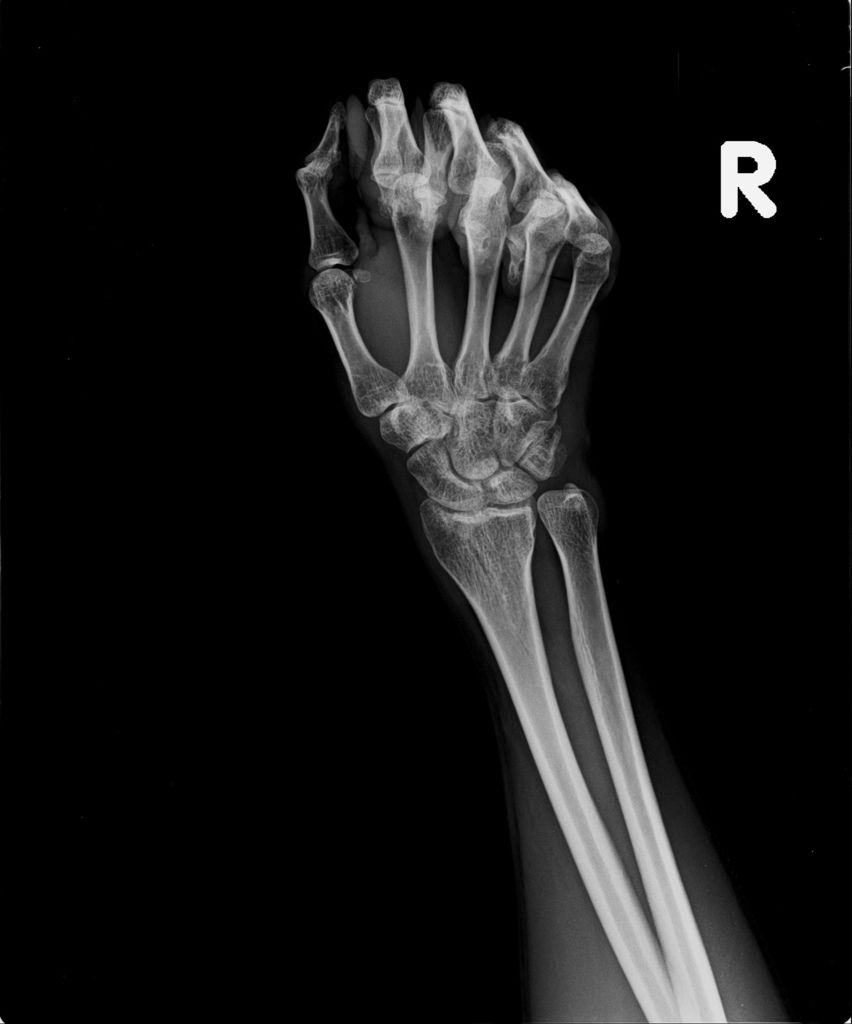

右手X光↓

進入門診前,我自認為手比腳恢復還快,因為比起一開始,手指比較能出力了,手腕可轉動的範圍也變大了。腳因一直用副木石膏固定住,不能動,所以也不知恢復多少。進入門診後,黃醫師說斷裂的骨頭都沒移位。手沒什麼進展(骨頭不會長那麼快),腳的部份下回再來復診時,可能會恢復的較快了。

手沒什麼進展這件事,讓我比較吃驚,詢問黃醫師,手如果也改用副木,會不會比較好,黃醫師說,他個人是認為沒什麼差。他看著X光片照出來的結果,說開刀或不開刀他覺得都差不多。